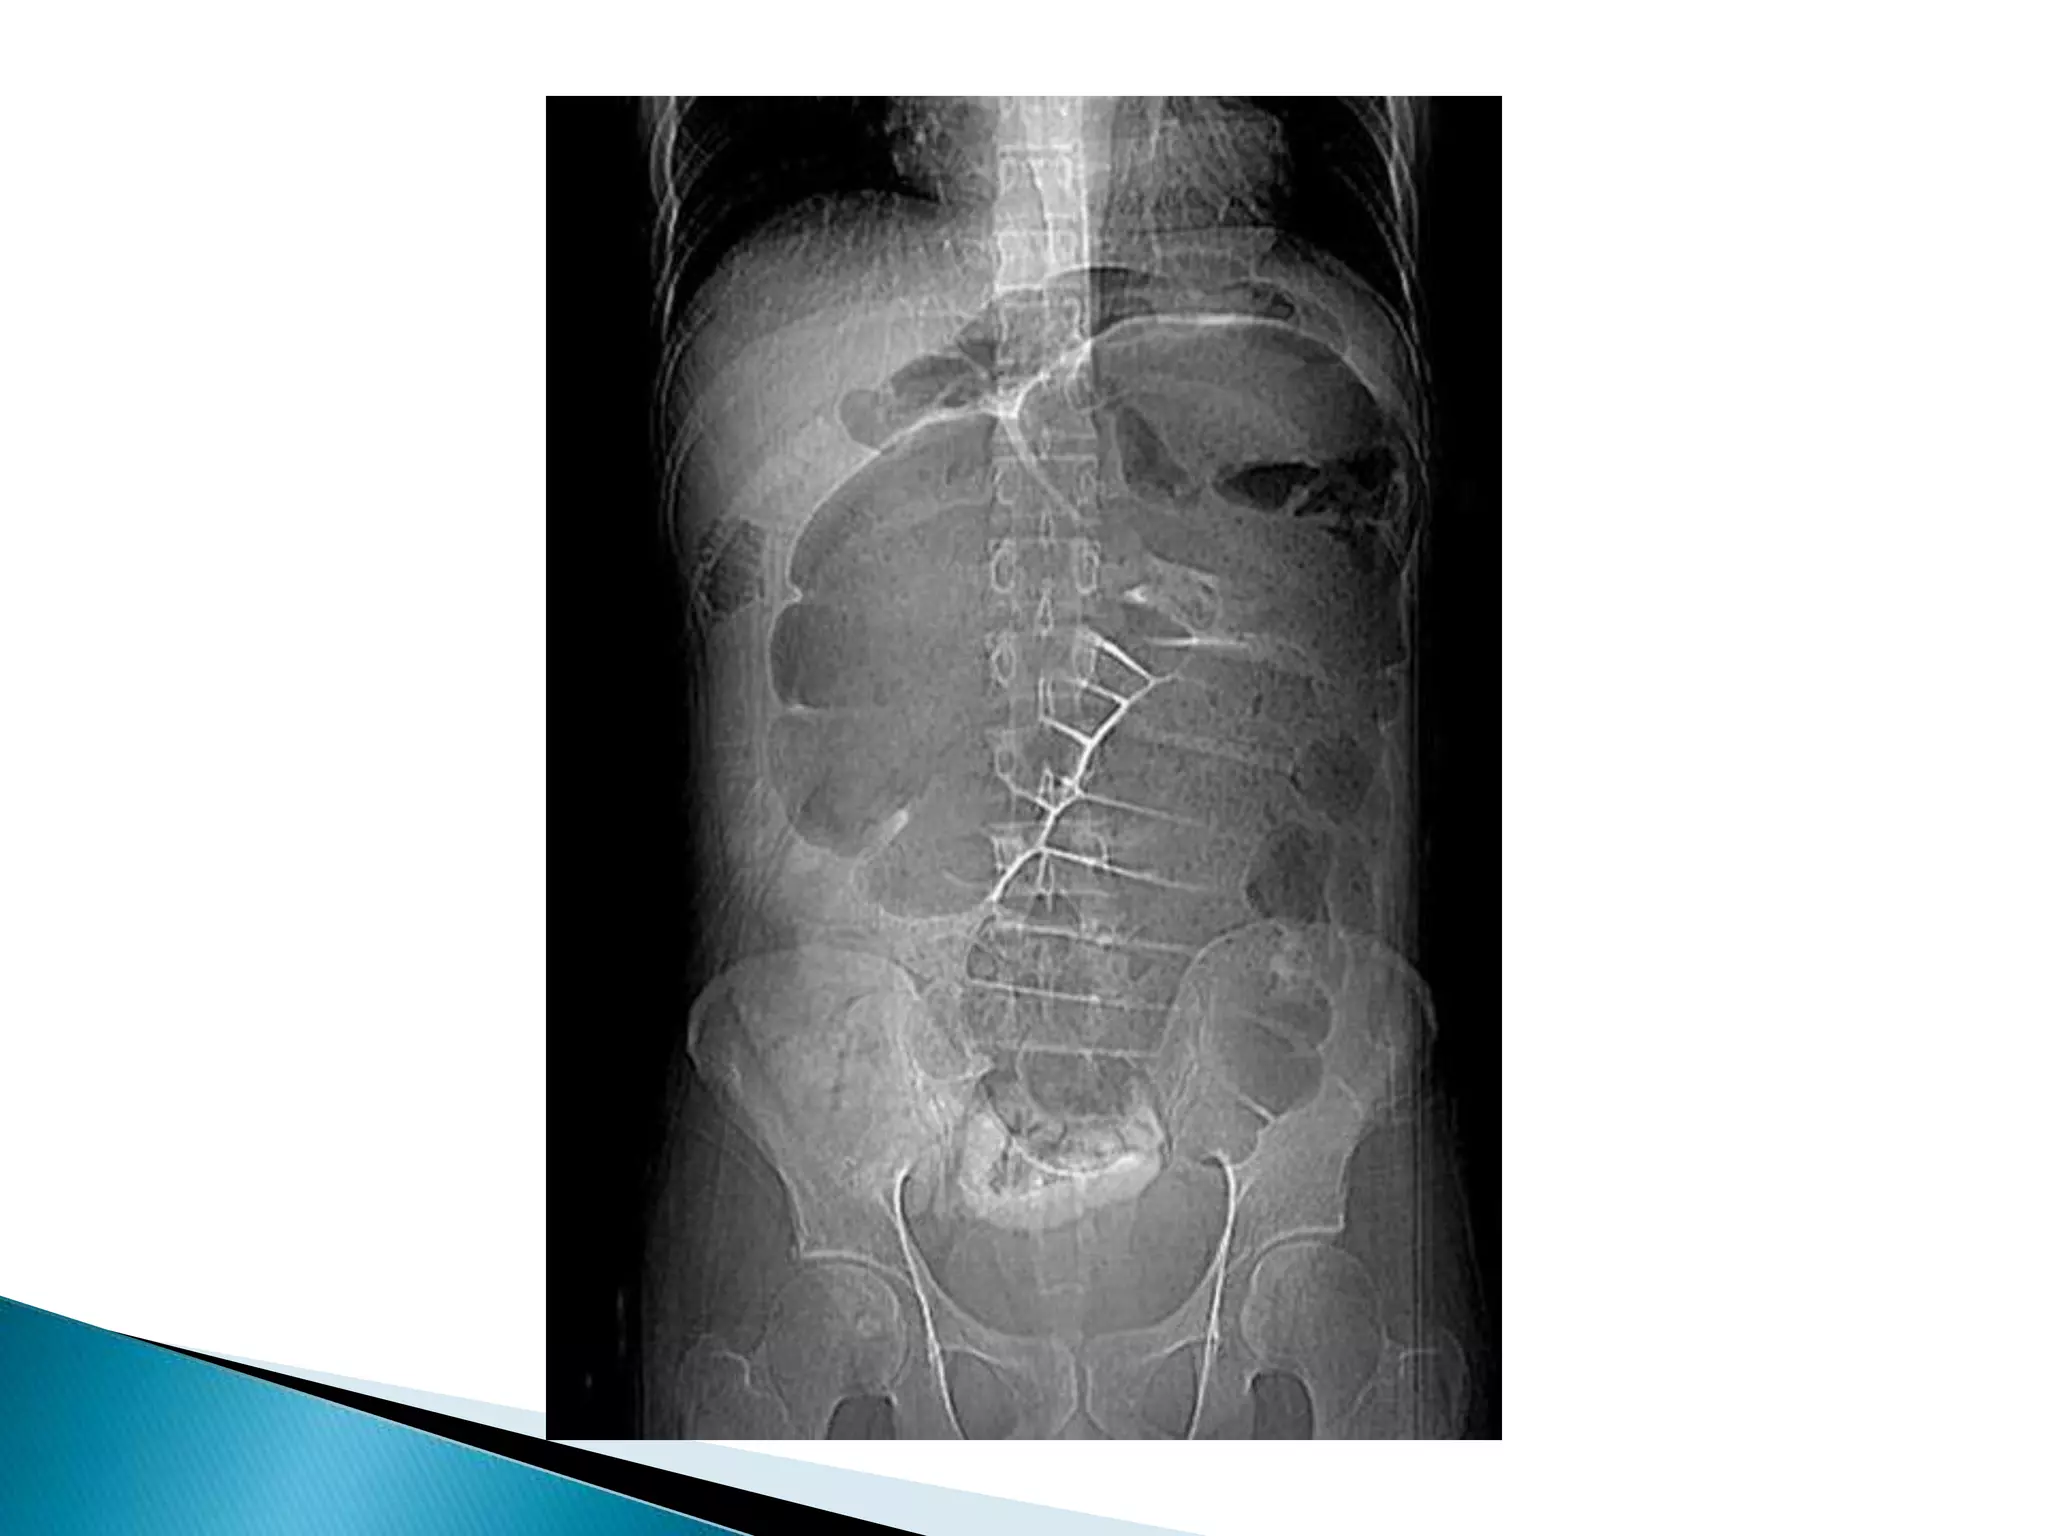

 20 year old woman presented to the ED with

12 hours of abdominal pain, nausea. and

vomiting low grade fever.

 No past surgical history

 PMH: Polycystic ovarian disease

Dilated cecum

Cecum

Contrast

In Descending colon

Barium Enema

Point of Obstruction

Ascending colon

 20 yearold woman presented to the ED with 12 hours of abdominal pain, nausea. and vomiting low grade fever.  No past surgical history  PMH: Polycystic ovarian disease

Barium Enema Point ofObstruction Ascending colon